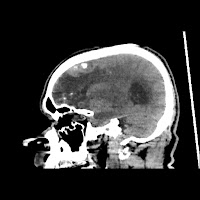

A 60 years old man with seizure since 12 years

Plan CT scan was done on 22 march 2016